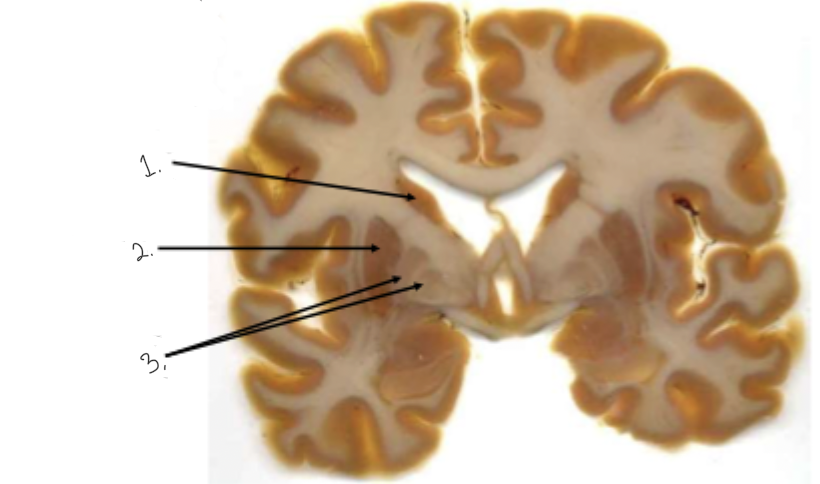

label this diagram

1: caudate nucleus

2: putamen

3: globus pallidus